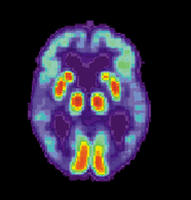

Los estudios actuales se basan en prevenir la aparición de dos estructuras en el cerebro de los pacientes de Alzheimer, las placas seniles y ovillos neurofibrilares, y en evitar la muerte neuronal que tiene lugar durante el proceso de la enfermedad. Sin embargo, según el doctor Martínez “una de las líneas de especial interés en el diagnóstico preclínico (antes de que la enfermedad comience a ser evidente) y específico”.